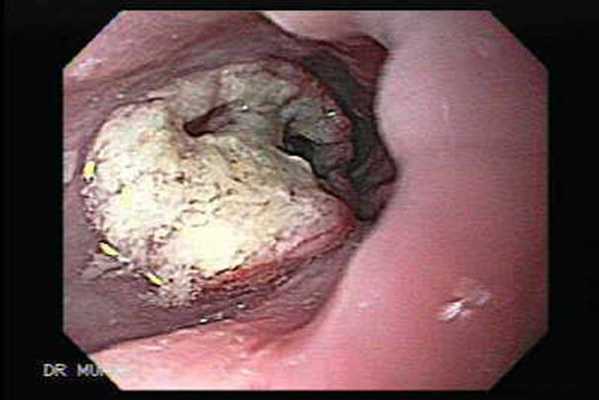

Эзофагогастродуоденоскопия (ЭГДС, ФГДС) позволяет не только выявить место расположения опухоли в пищеводе, но так же оценить протяженность поражения и характер ее роста. Однако самое важное то, что при эндоскопическом исследование возможно выполнить забор образца ткани опухоли (биопсия) для последующего исследования и определения клеточного типа опухоли (гистологическое исследование). Гистологическое исследование играет решающую роль в определении дальнейшей тактики лечения больного.

Эндоскопическая картина аденокарциномы

Эндоскопическая картина плоскоклеточного рака